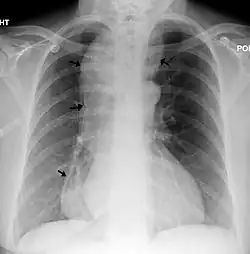

| A chest X-ray showing achalasia (arrows point to the outline of the massively dilated esophagus) | |